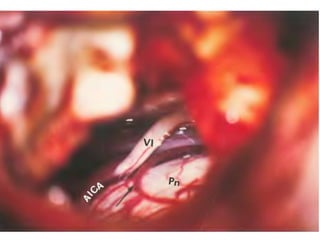

Right sided anterior petrosectomy on a cadaver dissection: intradural exposure

and operative field. PCA Petrous carotid artery; DPA drilled petrous apex; IPS

inferior petrosal sinus; BA basilar artery; VI 6th cranial nerve; AICA anterior inferior

cerebellar artery; P pons; V 5th cranial nerve

NOTE Inferior petrosal sinus at CLIVUS